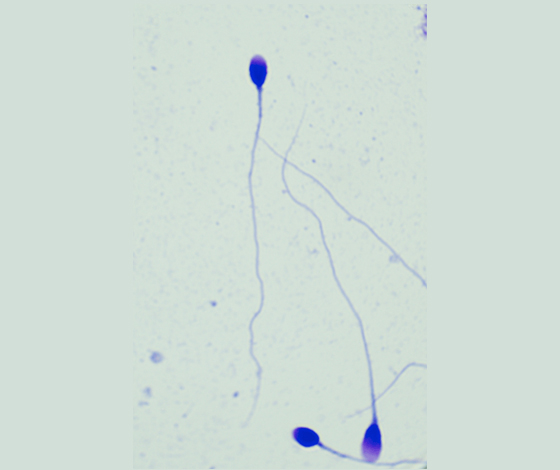

采用世界衛(wèi)生組織(WHO)推薦方法配制的精子形態(tài)快速染色液,對精子涂片進(jìn)行染色,精子頂體區(qū)、體部、尾部呈現(xiàn)不同的著色,觀察正常精子的形態(tài)百分比。

染色結(jié)果示意圖: